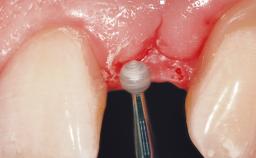

Immediate Flapless Placement of an Implant in a Maxillary Left Central Incisor Site

A 42-year-old female patient was referred to our clinic at the School of Dentistry of the University of São Paulo in November 2004, presenting a deficient restoration in the upper left central incisor. The clinical examination revealed no gingival retraction or any signs of gingival inflammation and, therefore, previous periodontal treatment was not considered. The patient presented a high lip line at full smile and a thin tissue biotype. This combination characterized a high-risk situation from an anatomic point of view, which required careful preoperative planning and cautious surgical execution.